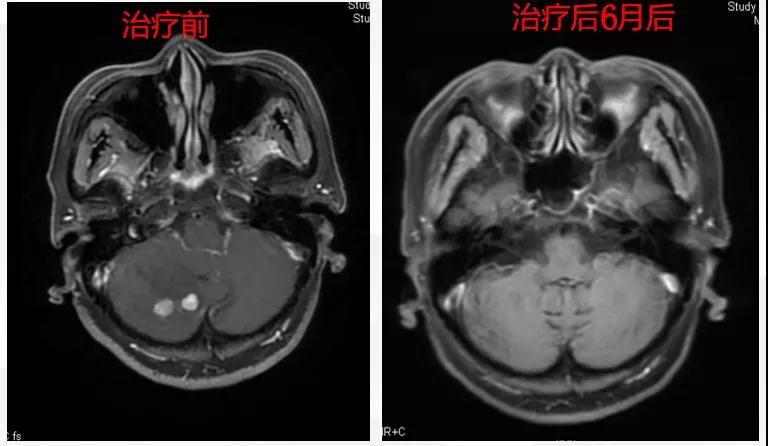

给予T-DM1治疗。治疗6个月后复查MR显示脑、肝、骨转移瘤均较前明显缩小,达到部分缓解(PR)(图2)。目前PFS已达10+个月。

图2

患者为ⅢA期(cT3N1M0)、三阳性乳腺癌,经AC-TH新辅助治疗达到降期(ypT2N0M0)。患者内分泌+抗HER2辅助治疗结束6个月时出现转移进展(脑、肝、骨),给予THP一线治疗,因无法耐受毒副作用而改为T-DM1,治疗6个月达到肝、脑、骨转移PR,患者目前中位PFS已超过10个月,T-DM1治疗过程中仅出现轻度CIT,且可自行恢复。